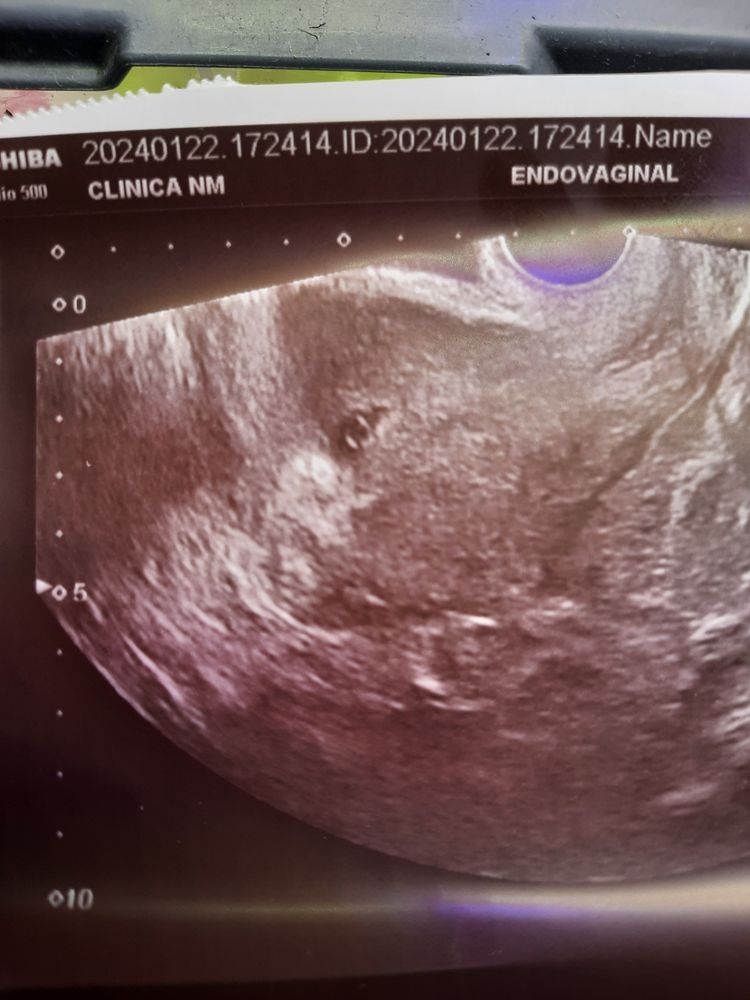

УЗИ 5.6 недель

Предыдущее узи было 16.01 - плодное яйцо 6 мм

Сегодня (22. 01) - плодное яйцо 12 мм, желточный мешочек 3 мм, хорион 2,6 мм - соответствуют 5.5 неделям

По сроку соответствует вроде все🙏 Но сказали матка в тонусе, поставила папаверин, больше никаких не было выделений. Жёлтое тело нашли, 17 мм. Живот немного побаливает.

Переживаю, что эмбриона ещё не увидели, но сказали это нормально + переживаю за выделения.